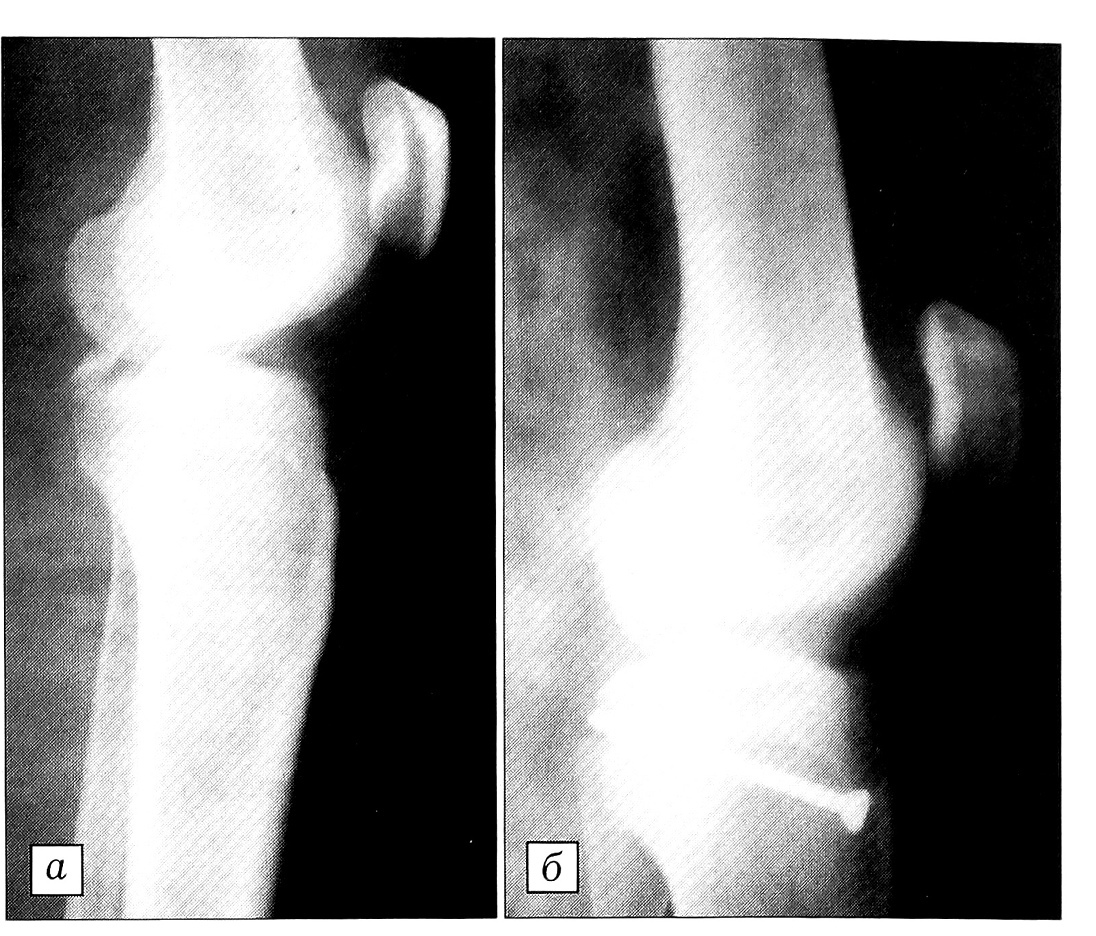

Больная Э.,13 лет, упала на уроке физкультуры с гимнастического коня, повредив правый коленный сустав. На рентгенограммах определяется отрывной перелом задневерхнего края большеберцовой кости (рис. 1, а). Костный фрагмент довольно больших размеров, смещение его превышает 1 см. При поступлении больной выполнена пункция коленного сустава, удалено 60 мл темной крови, в полость сустава введено 20 мл 2% раствора новокаина. После этого осторожно проведено исследование стабильности сустава. Выявлен положительный симптом «заднего выдвижного ящика». Наложена задняя гипсовая шина. На 3-и сутки после травмы произведено оперативное вмешательство. Положение больной на здоровом боку, конечность обескровлена. Из заднего доступа, через промежуток между сухожилиями полуперепончатой и полусухожильной мышц с одной стороны и медиальной головкой икроножной мышцы с другой вскрыт сустав, обнажено место перелома. Костный фрагмент вместе с фиксированной к нему ЗСК репонирован и закреплен в своем ложе винтом ретроградно (рис. 1, б). В течение 6 нед после операции продолжалась иммобилизация гипсовой шиной, затем проводились ЛФК и массаж, дозированная нагрузка. Больная осмотрена через год после операции: жалоб нет, объем движений полный, сустав стабилен.

Рис. 1. Рентгенограммы коленного сустава больной Э. до (а) и после (б) операции.